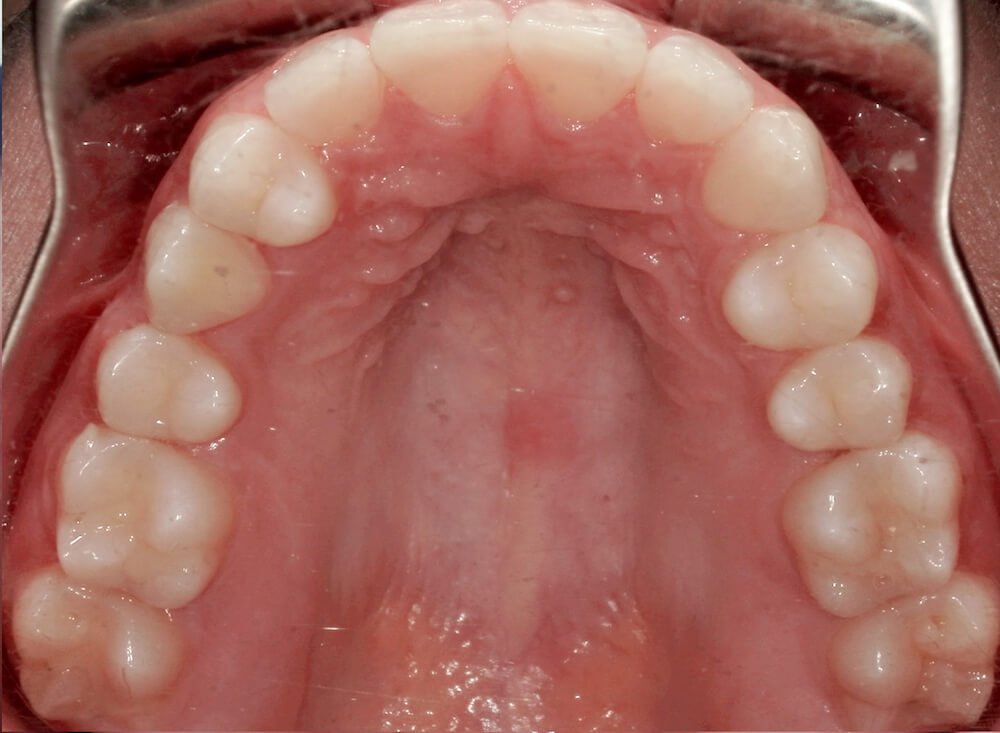

Severe crowding correction with Invisalign (24 months)

Before

After

Before

After